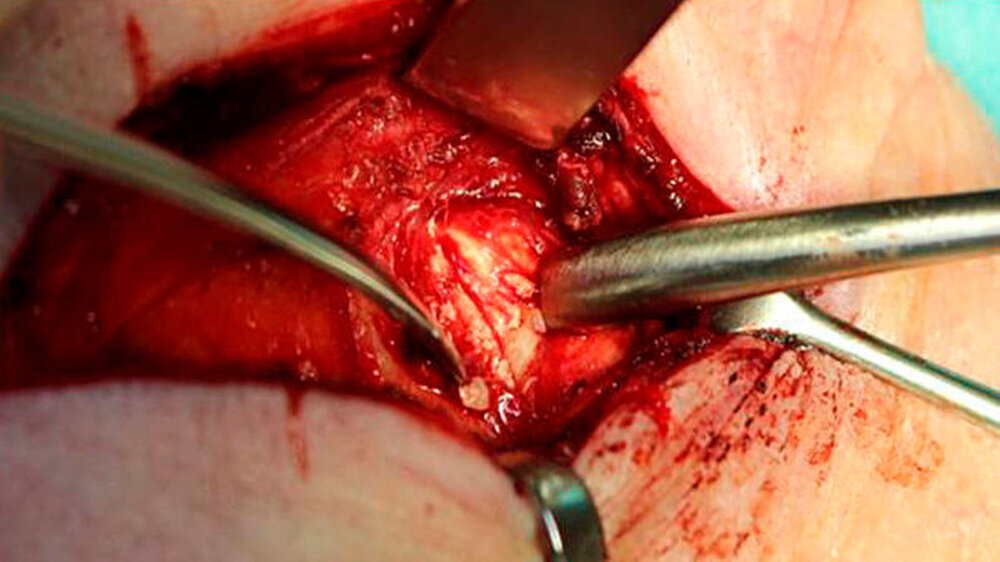

Das linke Kiefergelenk wurde über einen präaurikulären-temporalen Zugang unter Schonung des N. fazialis dargestellt. Nach Sichtbarwerden der deutlich verdickten Gelenkkapsel erfolgte die Inzision circa zwei Millimeter unterhalb der Gelenkgrube und Eingehen in den oberen Gelenkspalt (Abbildungen 5 und 6). Mithilfe der Schere wurde nun die Adhärenz des Discus artikularis von der Gelenkkapsel scharf getrennt und damit in den unteren Gelenkanteil eingegangen.

Jetzt wurde der zum Teil intraartikulär und zum Teil in der verdickten Gelenkkapsel liegende korpuskuläre Gelenkkörper unter ausgiebiger Spülung der Gelenkkapsel entfernt. Danach ließ sich der stark deformierte Gelenkkopf erkennen (Abbildung 7). Mithilfe von Diamantkugeln und einer maschinell betriebenen Feile wurde der Gelenkkopf ausgiebig modellierend osteotomiert und das Gelenk erneut inspiziert.

Die sich in situ befindlichen Fremdkörper wurden mit einem kleinen scharfen Löffel entfernt und das Gelenk nochmals gespült (Abbildung 8). Anschließend erfolgte eine adaptierende Naht der Gelenkkapsel und das Einbringen einer 8-er Redon-Drainage in die Wundhöhle. Nun erfolgten die Subkutan-Naht sowie die Hautnaht und das Anlegen eines sterilen Verbandes. Die entfernten Fremdkörper wurden zur patho-histologischen Untersuchung in Formalin aserviert und versandt.